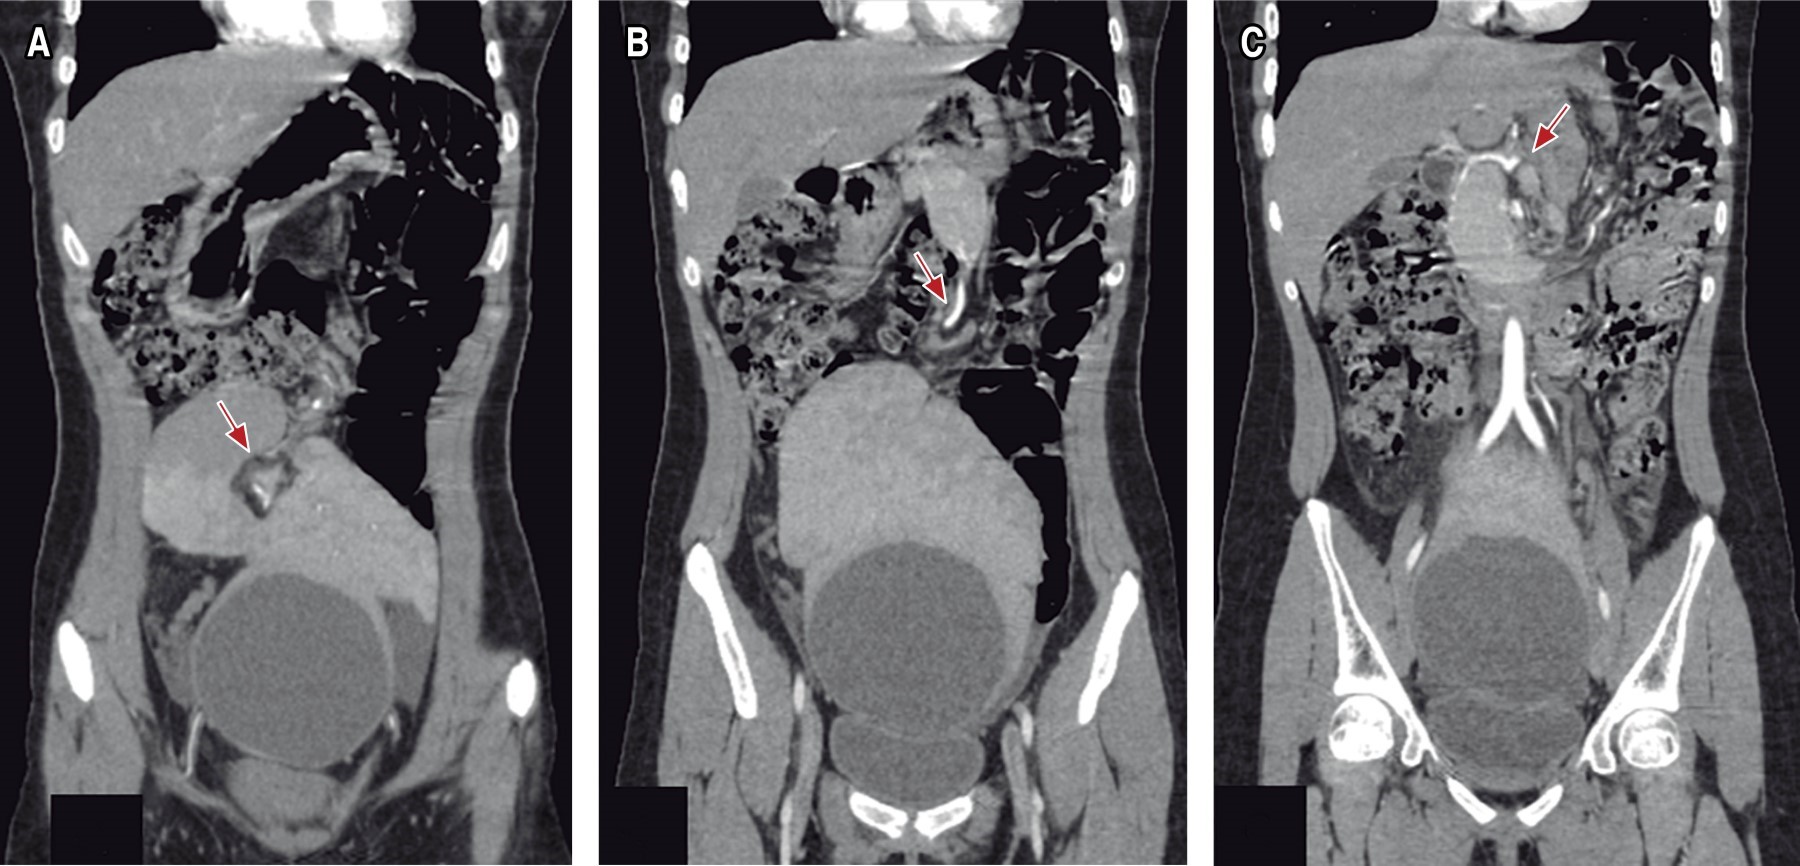

A la exploración física se logra palpar tumor delimitado, móvil, de aproximadamente 9 × 8 cm en cuadrante inferior izquierdo, sin datos de irritación peritoneal, se complementa abordaje con laboratorios en los que se reporta biometría hemática y química sanguínea dentro de parámetros normales, Ca-125 17 U/ml, tomografía abdominopélvica que reporta imagen compleja dependiente de ovario izquierdo (Figuras 1 y 2). Se decide realizar laparotomía exploradora electiva, donde se encuentra presencia de bazo errante a nivel pélvico con quiste de 9 × 9 cm (Figuras 3, 4 a 5), se realiza evisceración de bazo y drenaje de quiste, obteniendo 480 cm3 de contenido cetrino. Se solicita apoyo transoperatorio al Servicio de Cirugía General para la realización de esplenectomía, la cual se lleva a cabo con éxito. Útero, anexos y resto de vísceras sin alteraciones. Evolución postoperatoria adecuada, con egreso a las 24 horas de su ingreso, continuando con protocolo de paciente postesplenectomizado por externo.

El cuadro clínico cuando se presenta sintomático suele ser inespecífico, por lo que los estudios imagenológicos juegan un importante papel en el diagnóstico y de sus complicaciones. La tomografía abdominal contrastada es considerada el mejor estudio, aunque también pudiera ser útil el ultrasonido de abdomen. A menudo se identifica por su forma característica de "coma", sin observar el bazo en el cuadrante superior izquierdo; seguir el trayecto de los vasos esplénicos puede ayudar a identificar correctamente el bazo errante (Figuras 2 y 7).2

La presentación puede ser variable desde un hallazgo incidental, un tumor abdominal, abdomen agudo, incluso simular otras patologías,5 como en nuestro caso, el cual fue reportado erróneamente como tumor anexial. Entre las complicaciones se puede presentar torsión del pedículo vascular esplénico, lo cual puede provocar un infarto esplénico y/o trombosis de la vena esplénica, y dentro de las complicaciones más raras se ha descrito obstrucción intestinal por compresión, trombosis venosa portal, vólvulo gástrico e incluso asociación con vólvulo de cola de páncreas.4,5